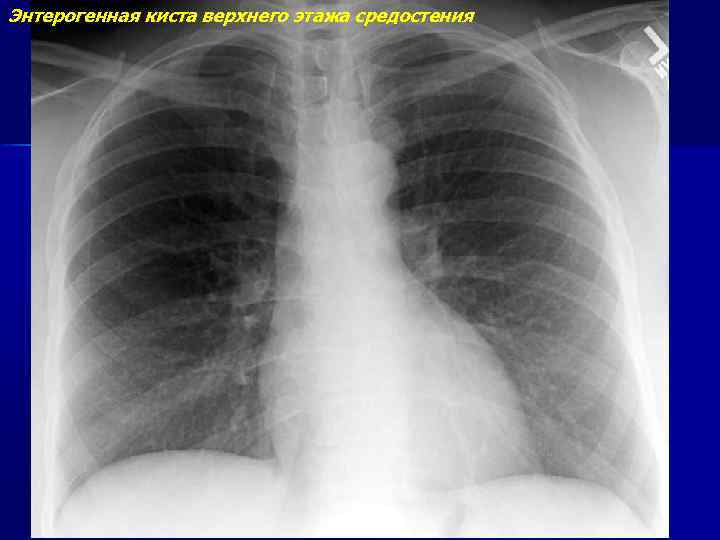

Рентгеновские снимки тератомы средостения: Диагностика и лечение